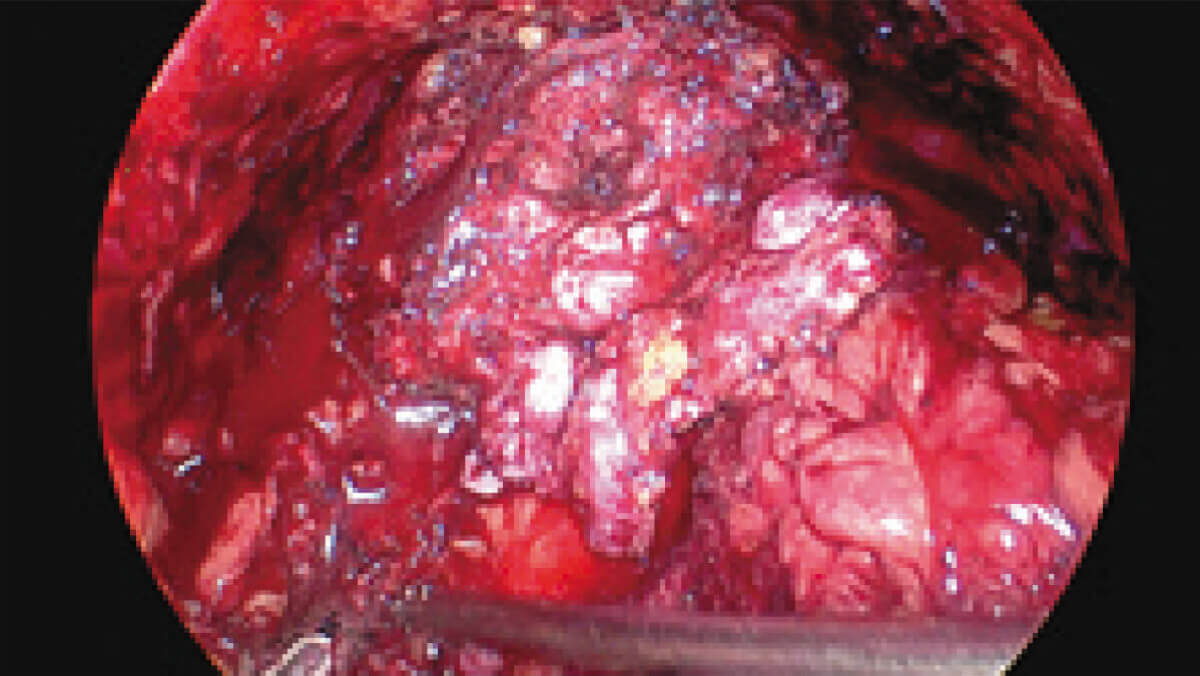

表面细节不遮盖

边界清晰,利于切缘评估

细微结构无伪影

避免术中误伤

荧光信号强弱分明

精准辅助临床决策